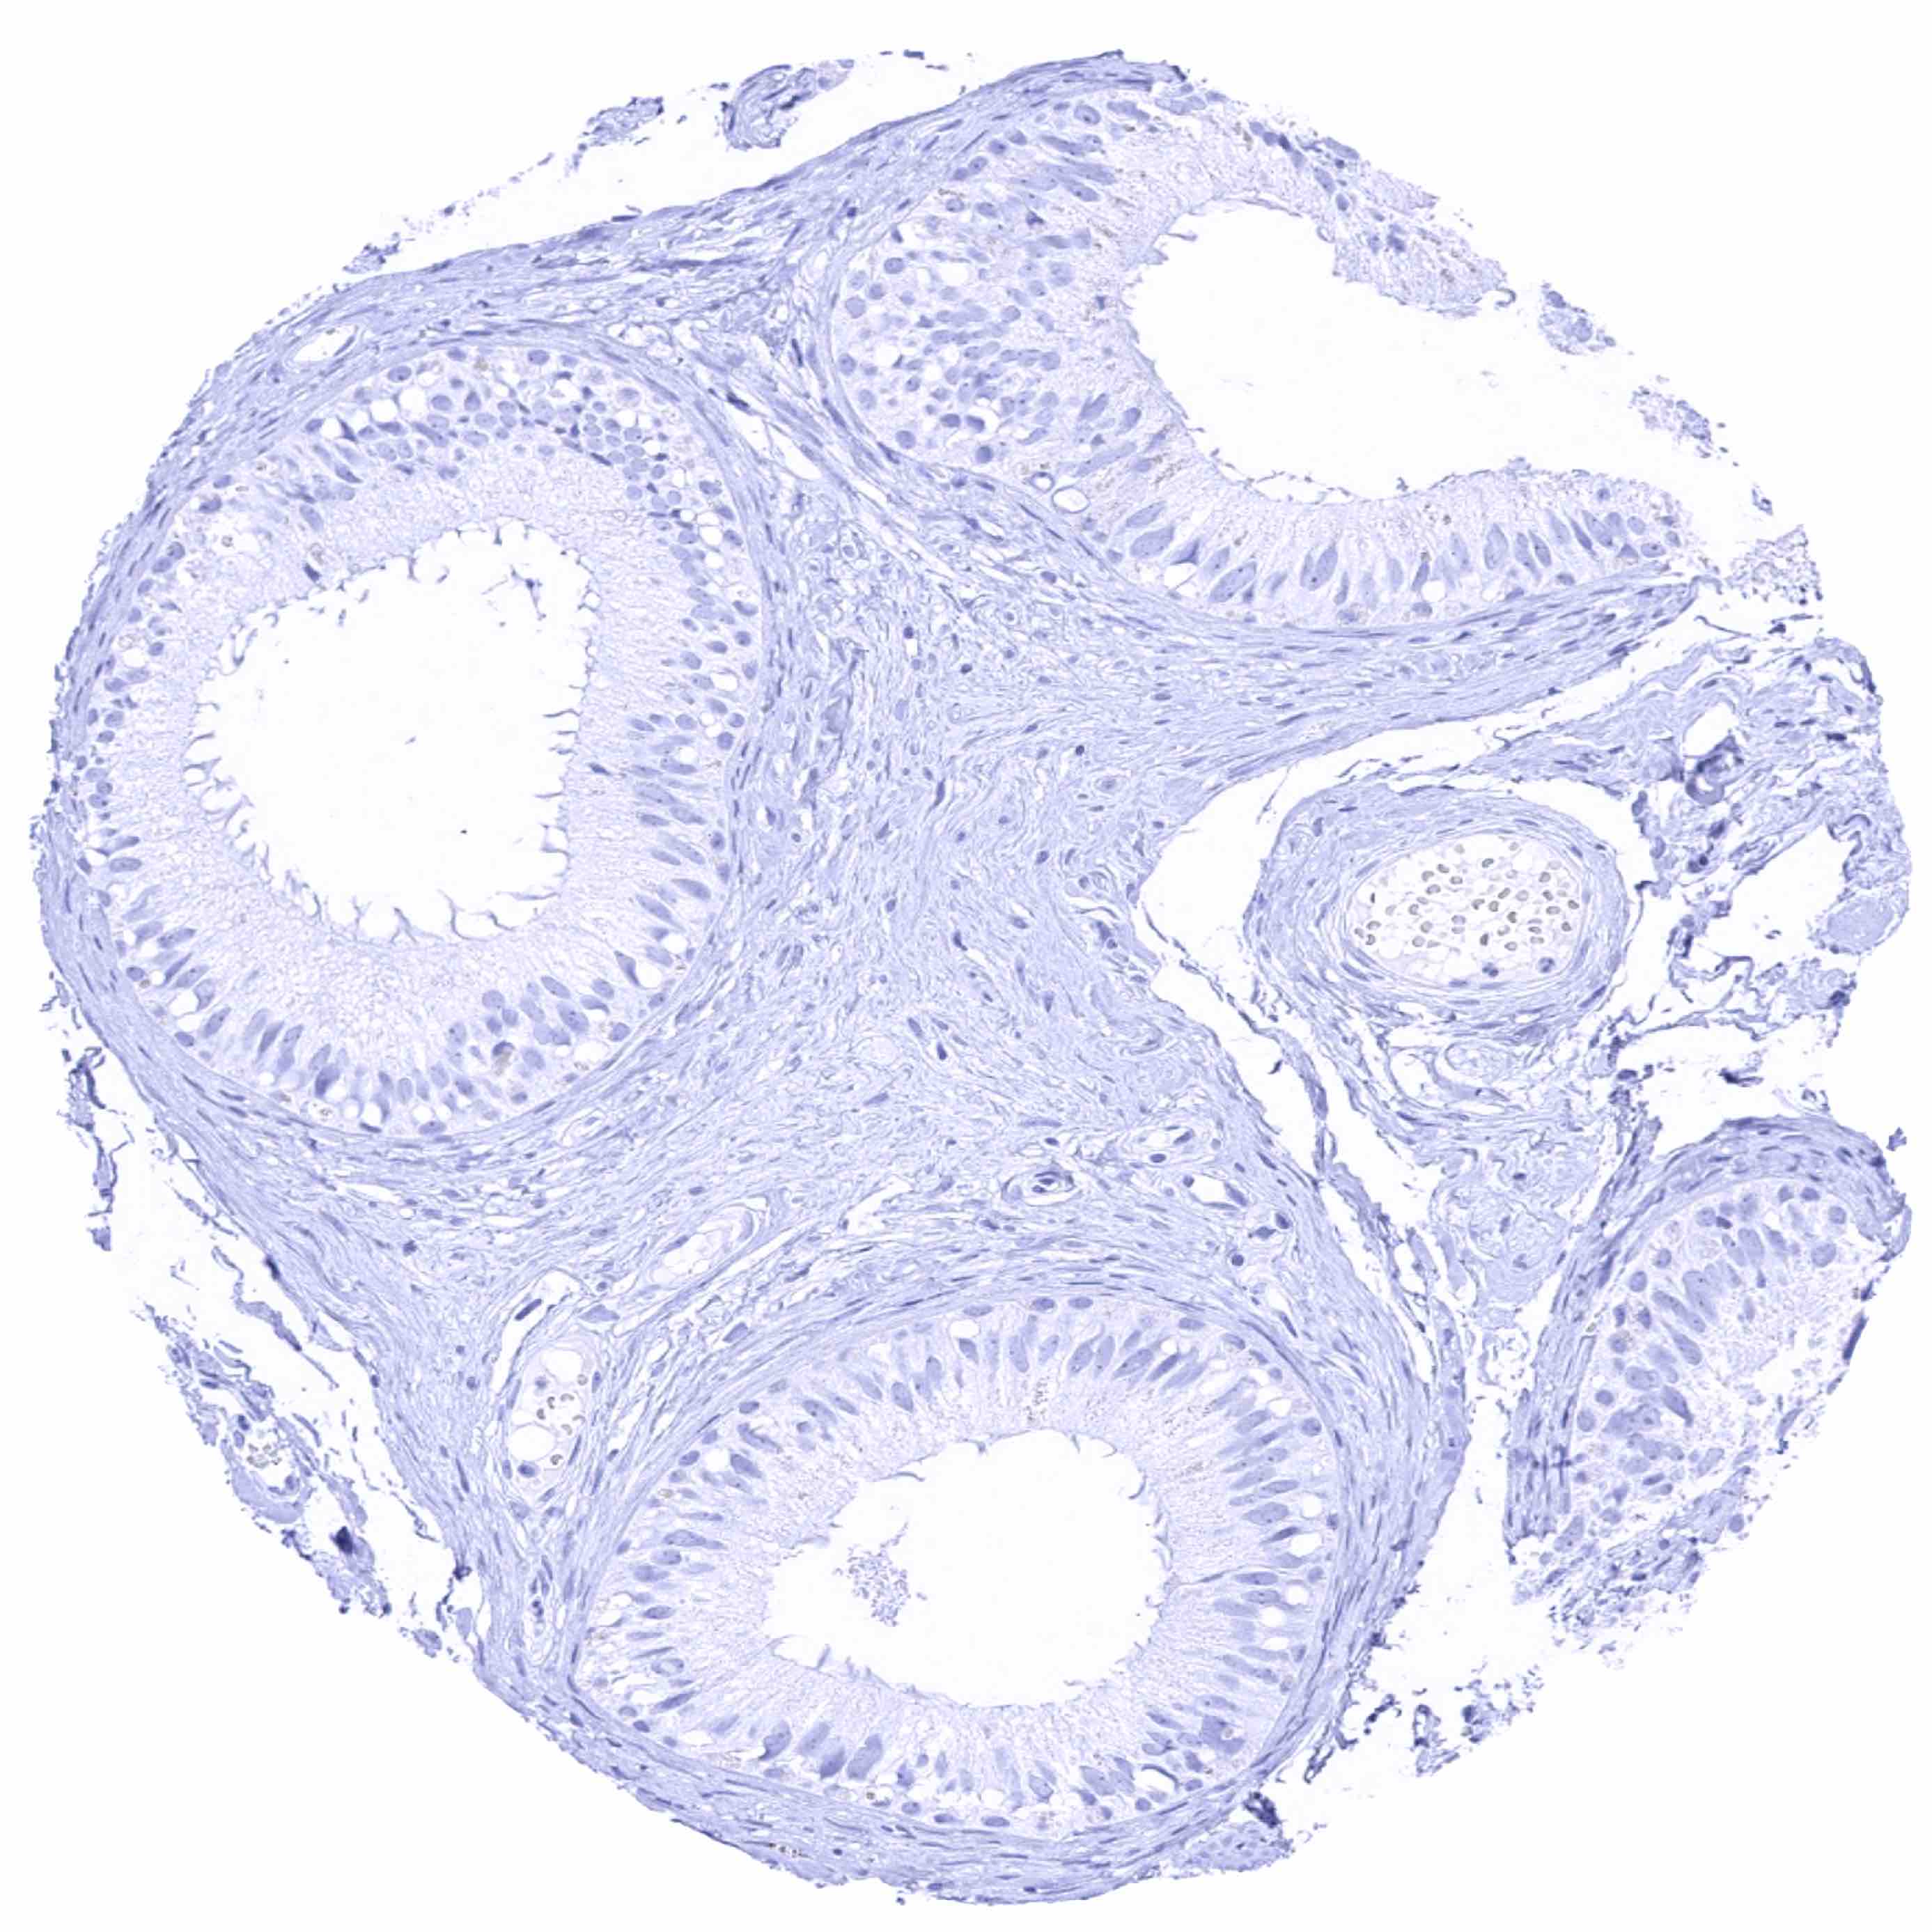

Seminal vesicle